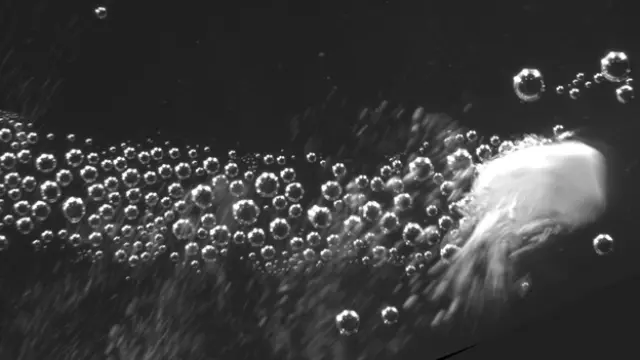

Sin embargo, las partículas autopropulsadas que han diseñado estos científicos tienen la capacidad de administrar coagulantes en el flujo sanguíneo para tratar una hemorragia interna grave, lo que supone un gran avance para la atención traumatológica. Se trata de un polvo compuesto por nanopartículas de carbonato de calcio que generan unos gases que les permiten autopropulsarse y llegar hasta la fuente de la hemorragia, aunque sea una zona interna de difícil acceso.